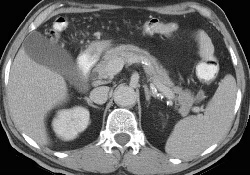

RADIOLOGY: GASTROINTESTINAL: GI: Case# 33673: DUODENAL WALL PSEUDOCYST WITH ASSOCIATED PANCREATITIS. 75 year old male with original suspicion of a pancreatic head mass. Current Exam: Comparison made with prior exam. There has been interval development of a 4x3.5cm pseudocyst located between the descending duodenum and the head of the pancreas, which probably involves the wall of the duodenum. Other smaller fluid collections are again identified in the region of the head of the pancreas. The small 1.3cm collection is unchanged. There has been interval improvement but persistent inflammatory changes in the region of the pseudocyst as well as the pancreatic head, descending duodenum, and right colon. Pancreatic pseudocysts are usually the sequelae of pancreatitis, most often associated with the subacute or chronic varieties. Peripancreatic fluid collections in the setting of acute pancreatitis are not pseduocysts. A pseudocyst is a cystic structure with a thick, fibrous wall and is not lined with epithelium (hence, it is not a true cyst). A pseudocyst may have a persistent connection to the pancreatic duct which may be demonstrated by ERCP. Typically, an uncomplicated pseudocyst will have a homogeneous water density. Increased density or inhomogeneity indicate some complicating factor such as hemorrhage or infection. Psuedocysts may also form in the walls of bowel (stomach, duodenum, colon) due to extension of pancreatic enzymes into the surrounding tissues.